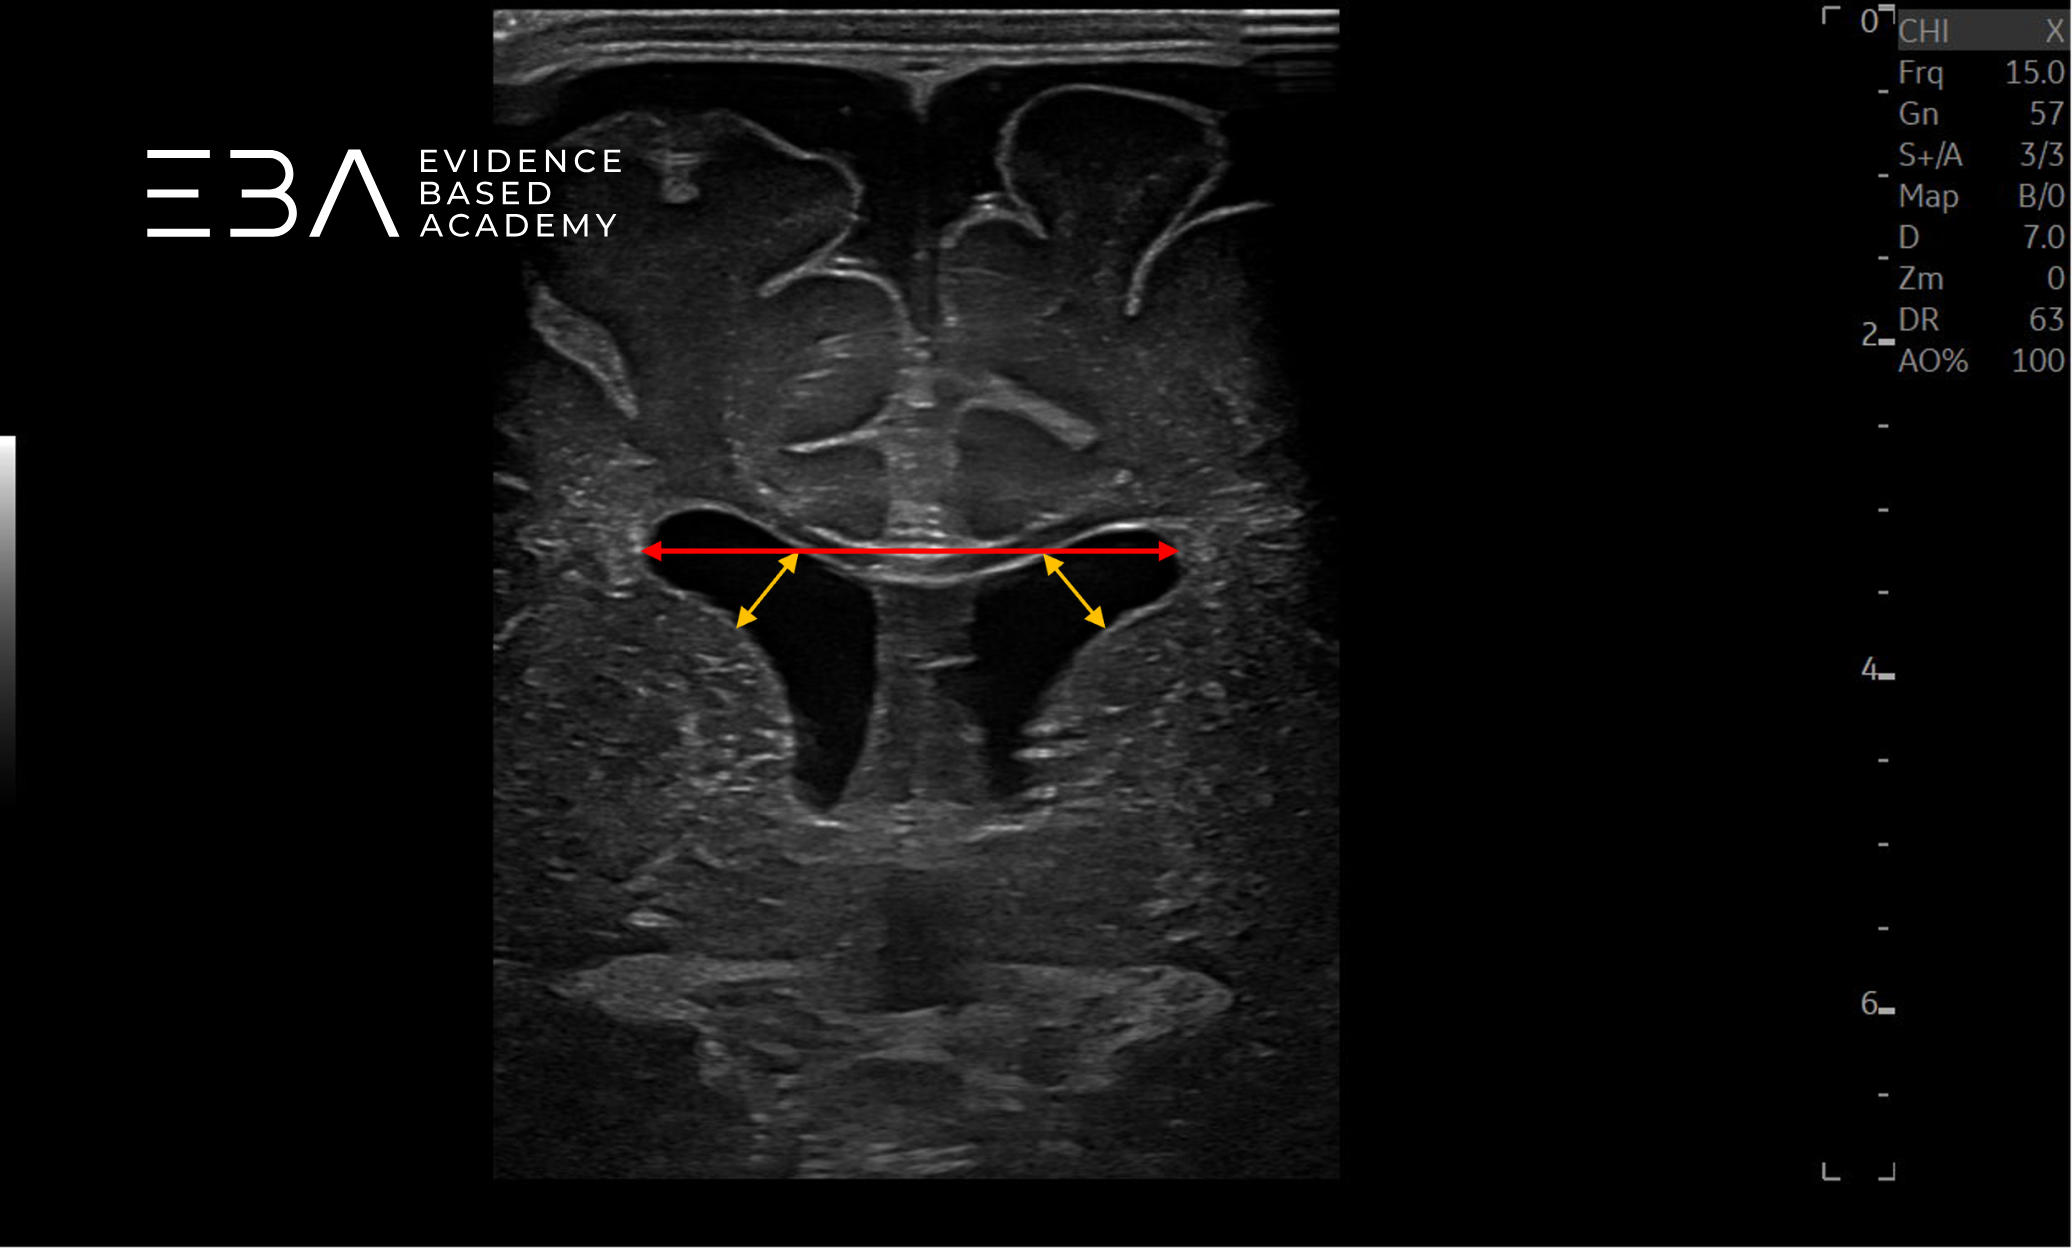

W praktyce klinicznej do monitorowania wielkości komór mózgowych stosujemy trzy pomiary (3): wskaźnik komorowy (ventricular index, VI), szerokość rogu przedniego (anterior horn width, AHW) oraz wymiar wzgórzowo-potyliczny (thalamo-occipital distance, TOD).

Wskaźnik komorowy (VI) to odległość między echem sierpu mózgu a boczną ścianą komory bocznej, mierzona w projekcji czołowej na poziomie otworu Monro. Trzon komory bocznej wybrano jako punkt referencyjny, ponieważ jest łatwo dostępny, symetryczny i posiada wyraźny punkt pomiaru, a zmiany jego wielkości odzwierciedlają zmiany w obrębie całego układu komór bocznych. Należy pamiętać, że bezwzględne wymiary komór zwiększają się fizjologicznie w pierwszych miesiącach życia, odzwierciedlając wzrost czaszki, a nie rzeczywiste poszerzenie komór (10). Dlatego pomiary komór należy odnieść do siatek centylowych uwzględniających wiek.

Szerokość rogu przedniego (AHW) w warunkach prawidłowych u noworodka wynosi <3 mm. Poszerzenie łagodne odpowiada wartościom 3-5 mm, umiarkowane 6-9 mm, a znaczne — powyżej 10 mm(9). Wymiar wzgórzowo-potyliczny (TOD) pozwala na ocenę tylnej części komory bocznej – poszerzenie rozpoznajemy przy wartości >24 mm (w tym samym badaniu 97. percentyl TOD wynosił około 19 mm u wcześniaków i 21 mm u noworodków donoszonych) (9). Pomiar TOD, mimo trudności technicznych, ma szczególną wartość kliniczną, ponieważ róg potyliczny może wykazywać najwcześniejszy i najszybszy wzrost w przebiegu pokrwotocznego poszerzenia komór (9).

zdj. c

Głowica liniowa. Czerwoną strzałką zaznaczono pomiar rozpiętości rogów czołowych komór bocznych, żółtą strzałką zaznaczono wskaźnik komorowy.

zdj. d

Głowica liniowa. Strzałkami zaznaczono pomiar szerokości rogów przednich.

zdj. e

Głowica liniowa. Czerwoną strzałką zaznaczono pomiar rozpiętości rogów czołowych komór bocznych, żółtymi strzałkami zaznaczono pomiar szerokości rogów przednich.